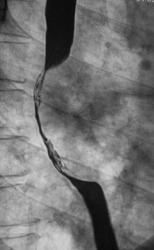

Рентгенограммы и их фрагменты.

Ниже представлены прицельные рентгенограммы пищевода, произведенные в процессе исследования данного пациента, в ортоположении водной взвесью сернокислого бария обычной консистенции.

Ниже рентгенограммы, произведенные на трохоскопе с применением сметанообразной и пастообразной контрастной взвеси.